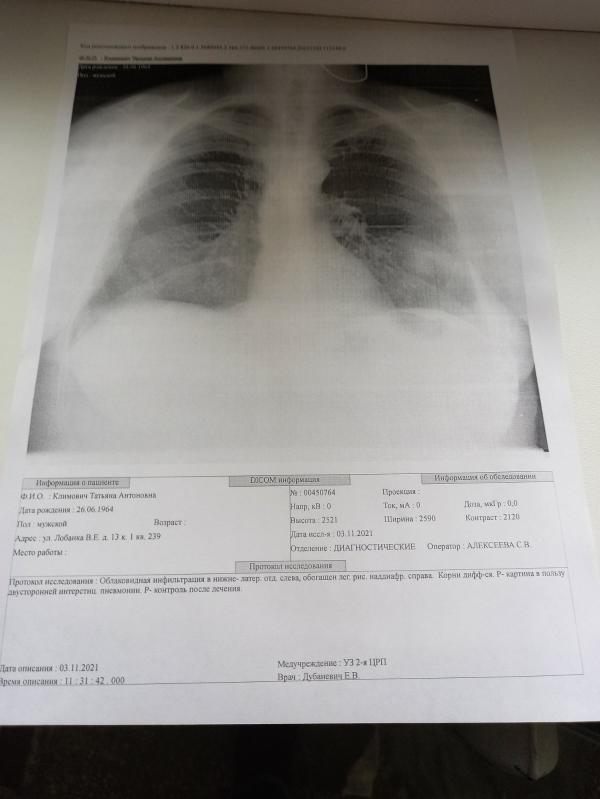

Насколько все плохо со снимками?

Девочки, кто разбирается в снимках. На сколько все плохо?

Пневмония с двух сторон, большая

Внизу описание снимка.